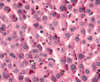

Kupffer cells - system of macrophages, known as Kupffer cells (KC), are found interspersed among the endothelial lining cells of Liver sinusoids (Si). these macrophages are larger than the epithelial cells and may be recognized by the presence of phagocytosed material within them. Kupffer cells may be demonstrated by injecting an animal intravenously with indian ink, as in this specimen. Some cells appear as large black smudges because they are filled with phagocytosed ink (arrows), whereas other cells possess only small quantities of the phagocytosed material (arrow heads). Note that much of the sinusoidal lining devoid of ink, indicating that the endothelial cells are probably not phagocytic.